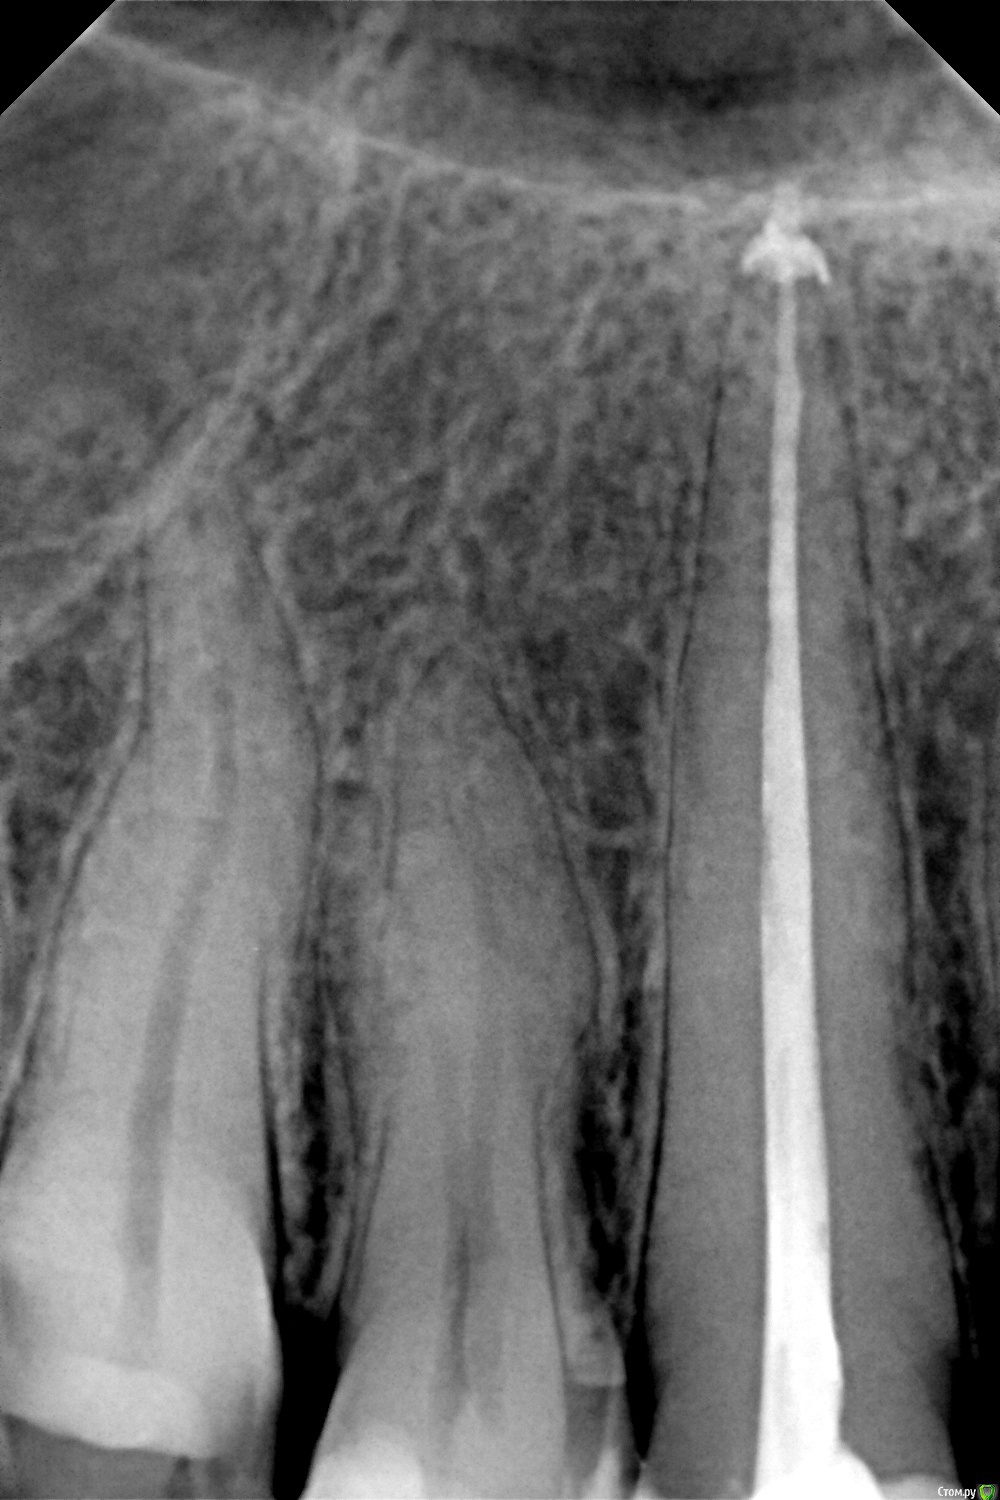

depression Опубликовано 3 декабря, 2015 Поделиться Опубликовано 3 декабря, 2015 (изменено) Доброе время суток. Пломбировали канал верхнего клыка - Dentofill + гуттаперча.В результате материал вышел за апекс. Доктор сказал,что со временем он рассосется и все будет ок.Подскажите,пожалуйста,можно и нужно ли это исправлять?P.S. Пломбировали 30.11,есть небольшая боль при накусывании. Спасибо. Изменено 3 декабря, 2015 пользователем depression Ссылка на комментарий

red_butler Опубликовано 3 декабря, 2015 Поделиться Опубликовано 3 декабря, 2015 это не много и не страшно 2 Ссылка на комментарий